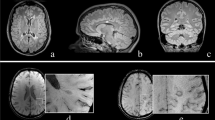

All studies defined EPVS as cerebrospinal fluid (CSF)-isointense punctuate structures on T1- and/or T2-weigted images, as well as their conforming path along penetrating arteries, e.g. in the semioval center or along the lenticulostriate arteries. All except one study assessed EPVS on T1- and T2-weighted images, the remaining study only used T2-weighted images to assess EPVS [7]. Acquired MR sequences per study are listed in Table 1. Most studies further report that EPVS can readily be discriminated from MS lesions or small lacunes by their hypointense appearance on fluid-attenuated inversion recovery [FLAIR] T2-weighted images, in contrast to the hyperintense appearance of MS lesions/lacunes on FLAIR T2-weighted images (Fig. 2). One study used phase-sensitive inversion recovery (PSIR) enabling enhanced T1 contrast [31], which may have resulted in higher sensitivity to detect EPVS [17].

Enlarged perivascular spaces (EPVS) are readily detectable on T1- and fluid-attenuated inversion recovery (FLAIR) T2-weighted (T1w, T2w) magnetic resonance imaging (MRI) as cerebrospinal fluid-isointense punctuate structures (red arrowheads) in the semioval center (a and b) and in the basal ganglia (c and d). In contrast, multiple sclerosis lesions appear hyperintense on FLAIR T2-weighted images (blue arrowhead in b)